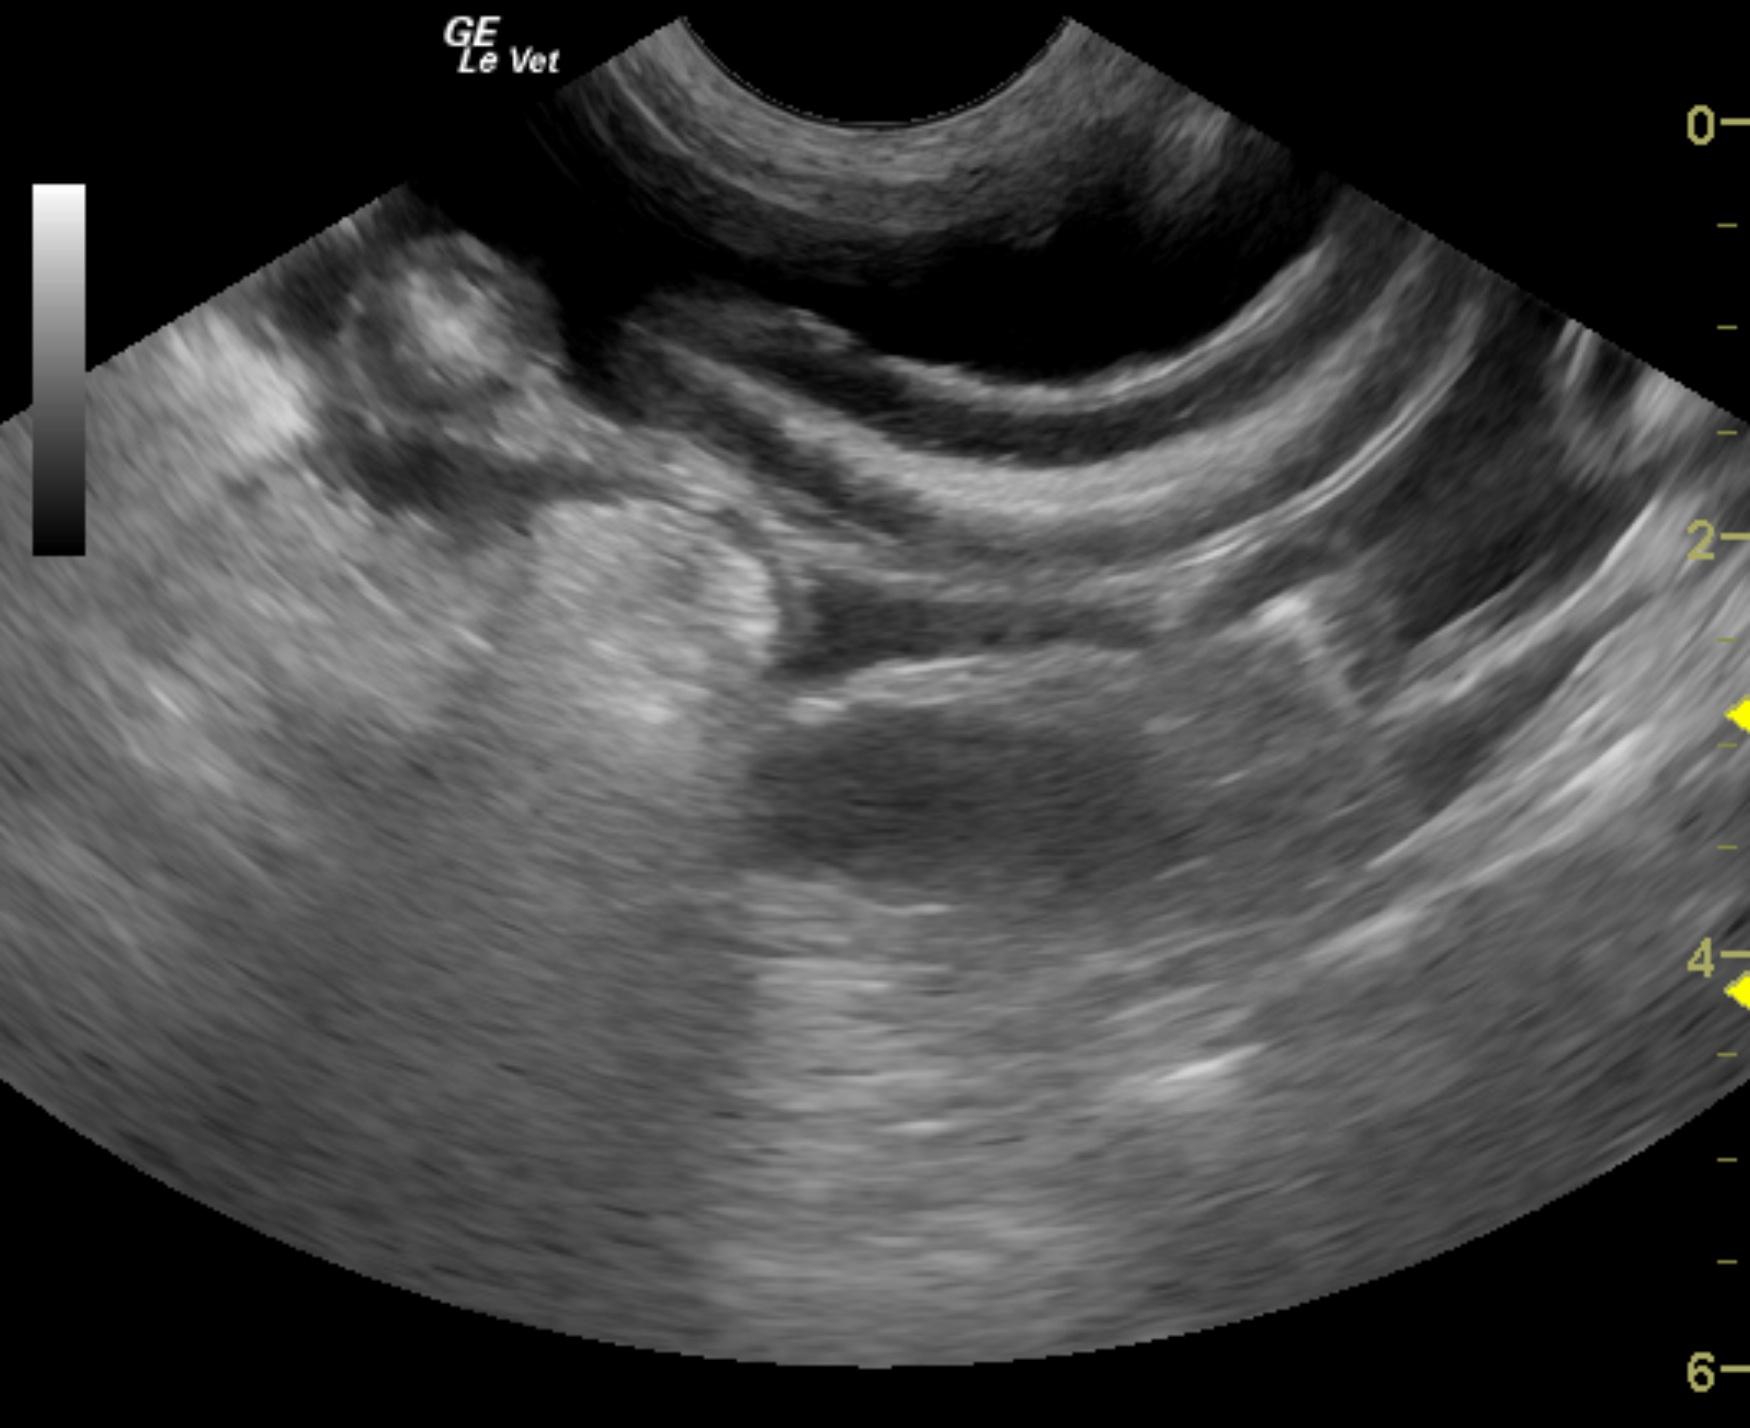

This 8 year old MN Jack Russull Terrier dog initially presented with abdominal distension and ascites. Chemistry revealed low total protein at 4.2, low albumin at 1.9, phosphorus low at 1.0, calcium low at 8.1, cholesterol was high at 332. Urine protein to creatinine ratio was high at 5.4, microalbuminuria was high at >30. Urinalysis reveled protein of 3+, blood 1+ and transitional epithelia elevated at 2-3.

This 8 year old MN Jack Russull Terrier dog initially presented with abdominal distension and ascites. Chemistry revealed low total protein at 4.2, low albumin at 1.9, phosphorus low at 1.0, calcium low at 8.1, cholesterol was high at 332. Urine protein to creatinine ratio was high at 5.4, microalbuminuria was high at >30. Urinalysis reveled protein of 3+, blood 1+ and transitional epithelia elevated at 2-3.